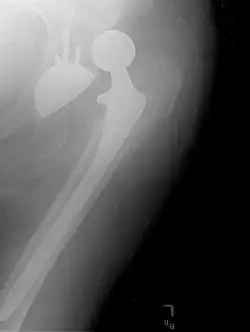

Hemiarthroplasty

Hemiarthroplasty is a surgical procedure that replaces one half of the joint with an artificial surface and leaves the other part unchanged. This class of procedure is most commonly performed on the hip after an intracapsular fracture of the femur neck (hip fracture). The procedure is performed by removing the head of the femur and replacing it with a metal or composite prosthesis. The most commonly used prosthesis designs are the Austin Moore and Thompson prostheses. A composite of metal and high-density polyethylene that forms two interphases (bipolar prosthesis) can be used. The monopolar prosthesis has not been shown to offer any advantage over bipolar designs. The procedure is recommended only for elderly/frail patients, due to their lower life expectancy and activity level. This is because over time the prosthesis tends to loosen or to erode the acetabulum.[101] Independently mobile older adults with hip fractures may benefit from a total hip replacement instead of hemiarthroplasty.[102]

Hip prosthesis for hemiarthroplasty. This example is bipolar, meaning that the head has two separate articulations. -

X-ray of the hips, with a right-sided hemiarthroplasty